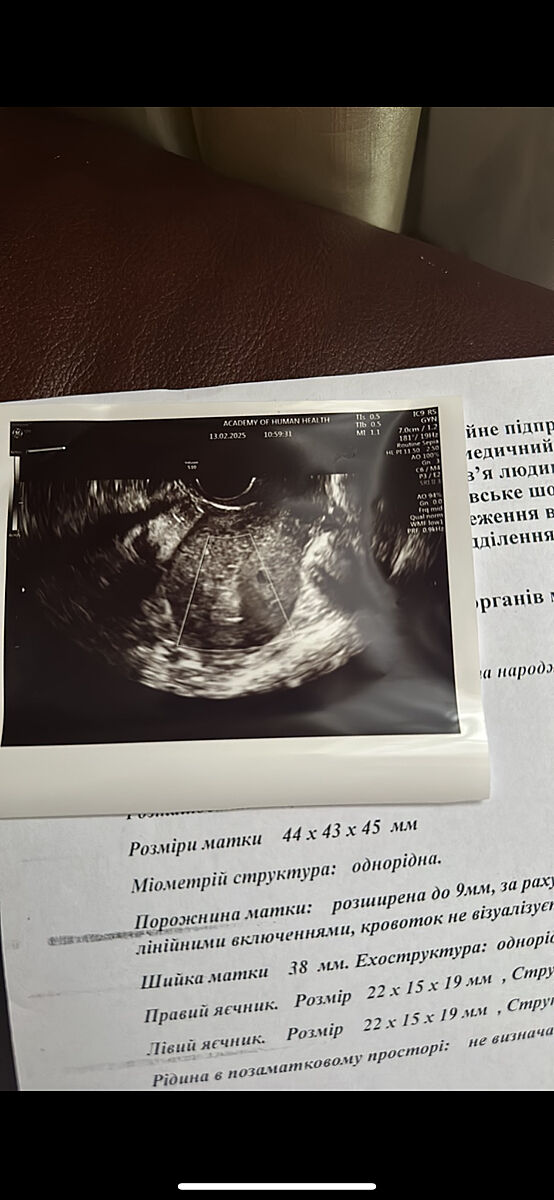

Пошла па узи, в заключение написали Міометрій структура: однорідна.

Порожнина матки: розширена до 9мм, за рахунок гетерогенного утворення з

лінійними включеннями, кровоток не візуалізується

Подскажите, сделала еще узи у супер специалиста

Смотрела вместе с врачам, который принимал роды, он зав отделения патологии в большом роддоме в Киеве у нас.

Сказали оба, что лесть и чистить что-то не надо, контроль через месяц и по результатам узи смотреть будем

Если вдруг кровотечение, быстро звонить ему